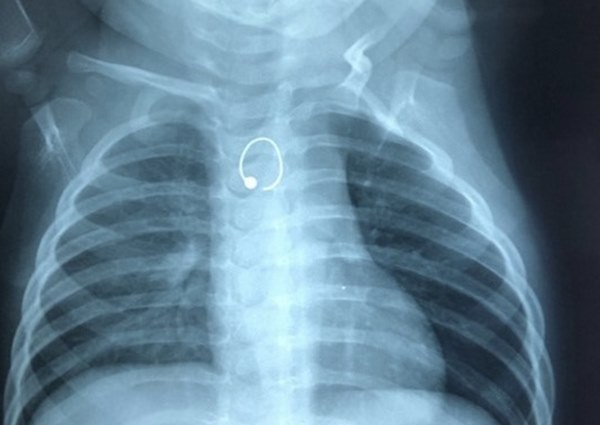

Ảnh chụp X-quang phát hiện dị vật.

Cách nhập viện 1 tuần, bé thở mệt hơn kèm khò khè và bú ít lại. Khi đến khám tại BV địa phương, bé không giảm triệu chứng và chụp X-quang. Ảnh chụp nghi ngờ có dị vật cản quang vùng thực quản.